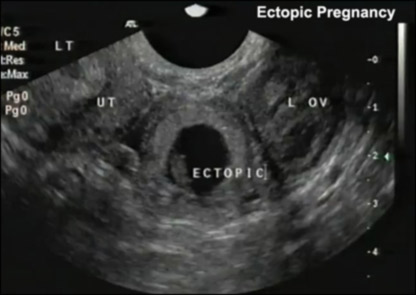

دوکتوران، اکسريز را برای خانم های حامله کار خطرناک دانسته و مناسب ترين معاينه را برای آنان ، التراسوند يا به گفته مردم معاينات تلويزيونی می دانند.

تا حد امکان کوشش شود که نزد خانم های حامله از التراسوند يا به اصطلاح مردم معاينه تلويزيونی استفاده شود.

چرا که اين معاينه مشکلات موجود در نقاط مختلف بدن، مانند:

جگر، پانقراص، کيسه صفرا ،معده، گرده ها ، مثانه و روده ها، رحم يا بچه دان، تخمدانها و جاهای ديگر بدن را نشان داده می تواند.

داکتر ملالی جاويد، متخصص التراسوند می گويد : معاينات تلويزيونی به واسطه سوند يا صدا اجرا می شود واز هيچ گونه شعاعی جهت اجرای اين معاينات استفاده نمی شود.

بنابرين به طفل ويا مادر، هيچ نقصانی متوجه نمی شود، بلکه اجرای آن در زمان حمل به خاطر دانستن وضيعت طفل در داخل رحم مادر بسيار ضروری هم است.